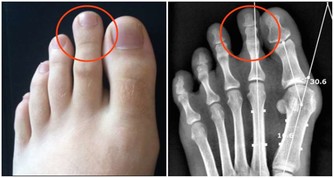

骨質疏鬆即骨質疏鬆症,是多種原因引起的一組骨病,骨組織有正常的鈣化,鈣鹽與基質呈正常比例,以單位體積內骨組織量減少為特點的代謝性骨病變。在日常的生活中,我們最常見的骨質疏鬆的症狀就是骨頭疼痛,身長縮短、駝背,容易骨折,還有就是呼吸功能下降。